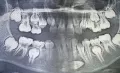

Мне 18 лет. Две недели назад заметила, что вверху за правым клыком растет зуб. Была в ужасе, ведь все зубы молочные у меня выпали. Сделала панорамный снимок, посоветовали вытягивать ретинированный зуб. Но врачи не смогли определиться какой зуб - молочный клык или резец.

Возможно ли вытянуть клык, который стоит напротив резца и расположен на расстоянии более 1 см от своего места в зубном ряду?

По снимку данный зуб - постоянный клык.